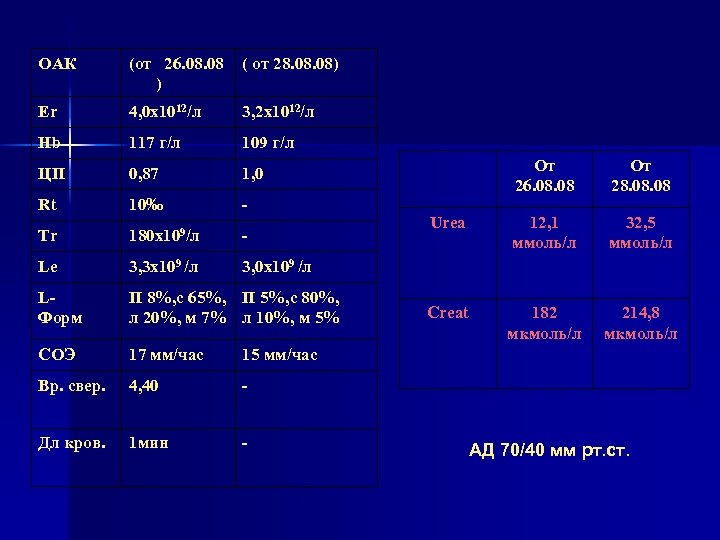

ОАК (от 26. 08 ) ( от 28. 08) Er 4, 0 х1012/л 3, 2 х1012/л Hb 117 г/л 109 г/л ЦП 0, 87 1, 0 Rt 10‰ - Tr 180 х109/л - Le 3, 3 х109 /л 3, 0 х109 /л LФорм П 8%, с 65%, П 5%, с 80%, л 20%, м 7% л 10%, м 5% СОЭ 17 мм/час 15 мм/час Вр. свер. 4, 40 - Дл кров. 1 мин - От 26. 08 От 28. 08 Urea 12, 1 ммоль/л 32, 5 ммоль/л Creat 182 мкмоль/л 214, 8 мкмоль/л АД 70/40 мм рт. ст.

ОАК (от 26. 08 ) ( от 28. 08) Er 4, 0 х1012/л 3, 2 х1012/л Hb 117 г/л 109 г/л ЦП 0, 87 1, 0 Rt 10‰ - Tr 180 х109/л - Le 3, 3 х109 /л 3, 0 х109 /л LФорм П 8%, с 65%, П 5%, с 80%, л 20%, м 7% л 10%, м 5% СОЭ 17 мм/час 15 мм/час Вр. свер. 4, 40 - Дл кров. 1 мин - От 26. 08 От 28. 08 Urea 12, 1 ммоль/л 32, 5 ммоль/л Creat 182 мкмоль/л 214, 8 мкмоль/л АД 70/40 мм рт. ст.